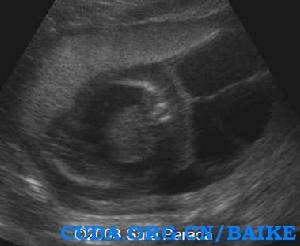

超聲發現:囊性水囊瘤是嚴重X單體的早孕和中孕期典型的徵象。妊娠晚期,孤立的胸腔積液和廣泛的水腫可以發生。最常見的心臟畸形是主動脈弓縮窄。